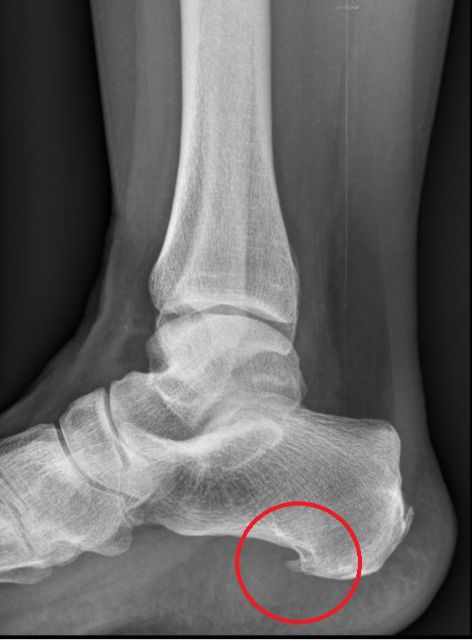

Bandverletzungen führen zu Instabilitäten und Schmerzen. Mittelfristig besteht ein ausgeprägtes Unsicherheitsgefühl und Abnützungen der großen Gelenke treten häufig als Folge dieser Verletzungen auf.

Im Zuge von Bandverletzungen kommt es häufig zu begleitenden Knorpelschäden und Sehnenverletzungen und mitunter auch zu knöchernen Verletzungen.

Degenerative Bandverletzungen treten vor allem im Rahmen eines sogenannten „erworbenen Plattfußes" auf. Dabei wird abgesehen von einer Überdehnung bzw Ruptur des Springligaments an der Innenseite des Fußes die Tibialis posterior Sehne schmerzhaft insuffizient und eine Fehlstellung in Form eines Plattfußes tritt als Hauptsymptom auf.